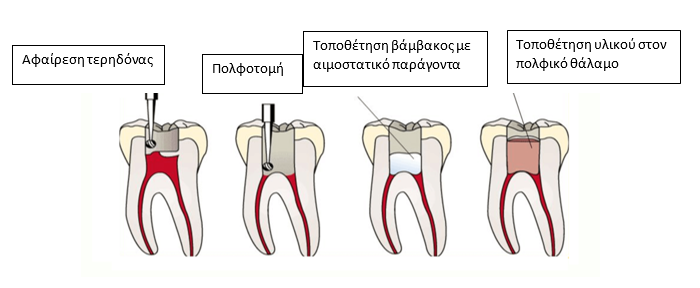

Τι είναι η πολφοτομή;

Η πολφοτομή είναι μια θεραπευτική αντιμετώπιση των νεογιλών δοντιών ή των νεαρών μονίμων δοντιών, τα οποία έχουν τερηδονιστεί ή έχουν υποστεί οδοντικό τραύμα ( πχ κάταγμα αδαμαντίνης-οδοντίνης). Ας εστιάσουμε στην περίπτωση τερηδονισμού, όταν κατά την αφαίρεση της τερηδόνας γίνει αποκάλυψη του πολφού και αυτός δεν παρουσιάζει νέκρωση ή μη αντιστρεπτή φλεγμονή, προβαίνουμε σε πολφοτομή. Η πολφοτομή εξασφαλίζει την ζωτικότητα του δοντιού και την παραμονή του στον φραγμό μέχρι την απόπτωση του (αν μιλάμε για νεογιλό). Η τεχνική είναι ανώδυνη, καθώς γίνεται υπό τοπική αναισθησία, ασφαλής και γρήγορη.